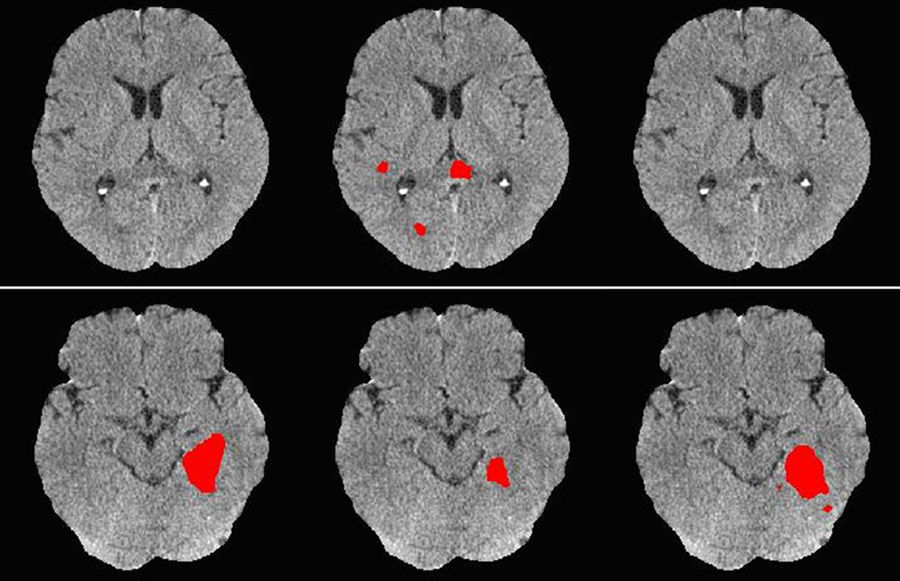

AI-powered systems can analyze brain scans within seconds, identifying signs of ischemic or hemorrhagic stroke long before human review is complete. This speed gives doctors more time to initiate life-saving interventions like thrombolysis or mechanical thrombectomy.

Precisely annotated datasets are critical for training AI models to recognize minute, clinically relevant features that may be missed due to human limitations. This capability directly reduces the rate of false negatives, thereby significantly enhancing diagnostic reliability, particularly during the critical early stages of stroke. The resulting early detection drives superior clinical performance, mitigating the risks associated with misdiagnosis and eliminating costly diagnostic delays.

AI-driven segmentation and radiomics extraction are fueling new stroke research directions — from automated lesion quantification to deep phenotyping of vascular territories. These advancements support faster hypothesis testing and drug discovery in cerebrovascular research.